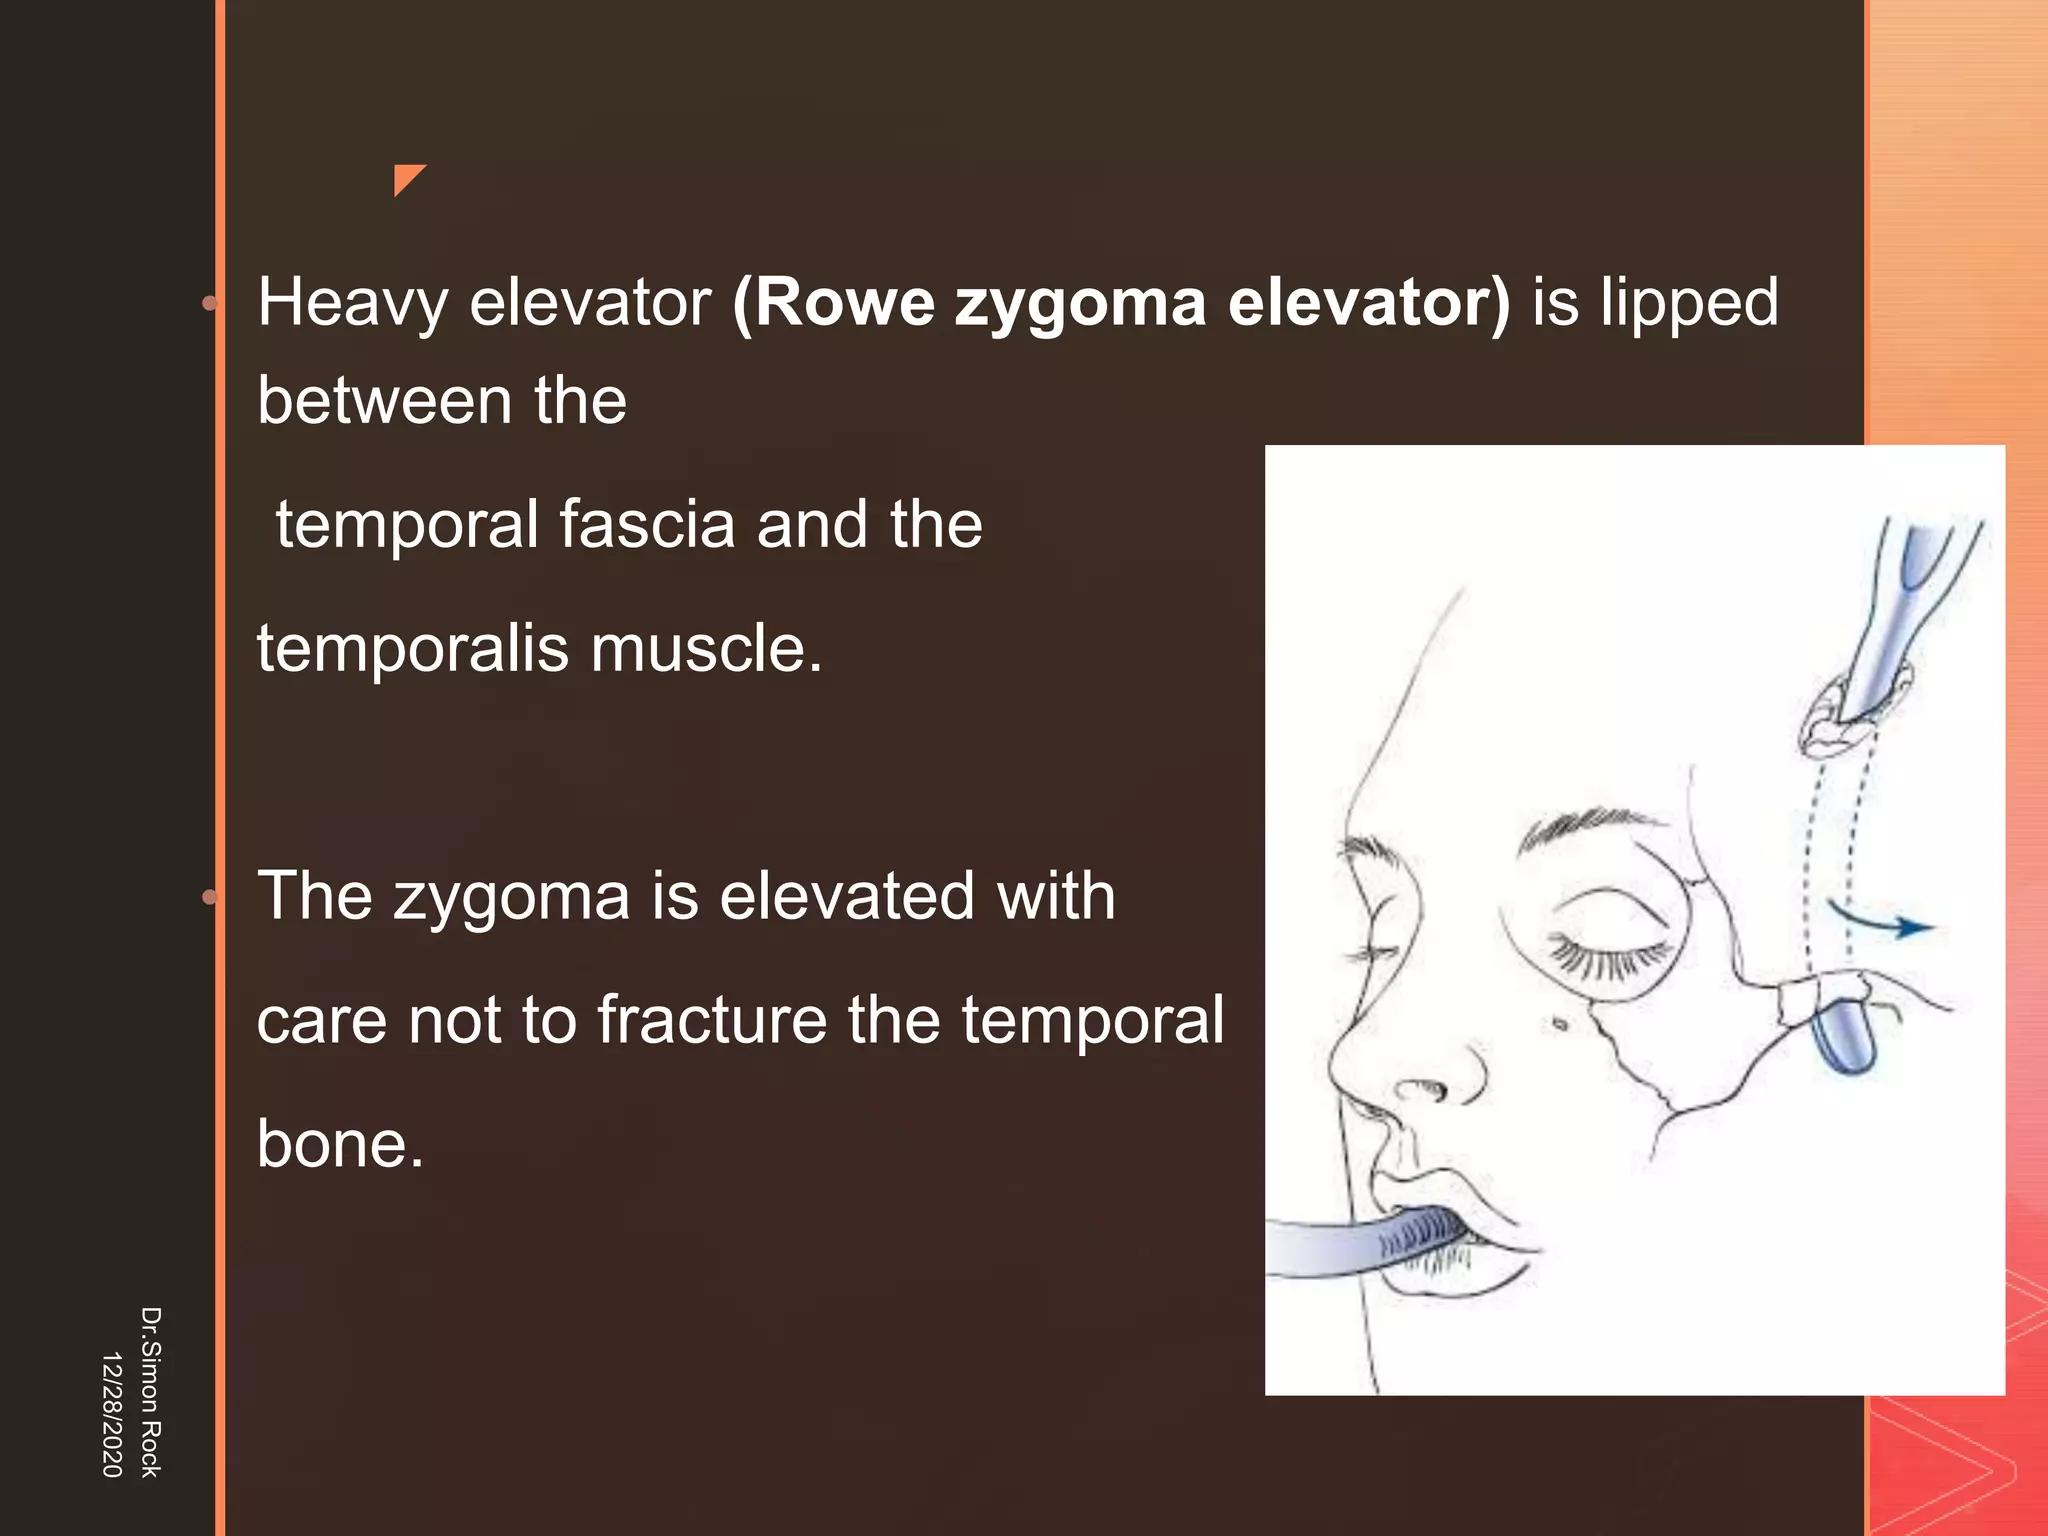

This document discusses the anatomy and fractures of the zygomatic bone. It notes that the zygoma forms the cheekbone and articulates with several other facial bones. Zygomatic fractures most commonly occur in the arch or body due to blunt trauma. Diagnosis involves checking for diplopia, ecchymosis, and other signs of orbital or facial bone involvement. Treatment may involve closed or open reduction based on the severity of displacement. Closed reduction techniques try to elevate the bone back into position without surgery, while open reduction requires surgical exposure and fixation of the fracture site.